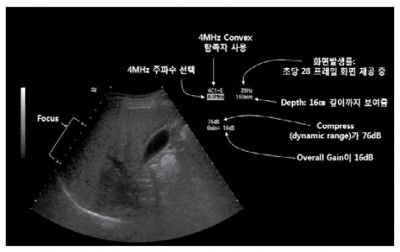

지금까지 조절했던 여러 가지 기능과 영상 표시에 대한 정보가 모니터에 표시된다.

실전예시 ① : Image noise를 줄이는 방법

Overall gain을 줄이고, 주파수를 높이거나, compress를 높인다. 또는 Harmonic image 및 compound image를 사용한다.